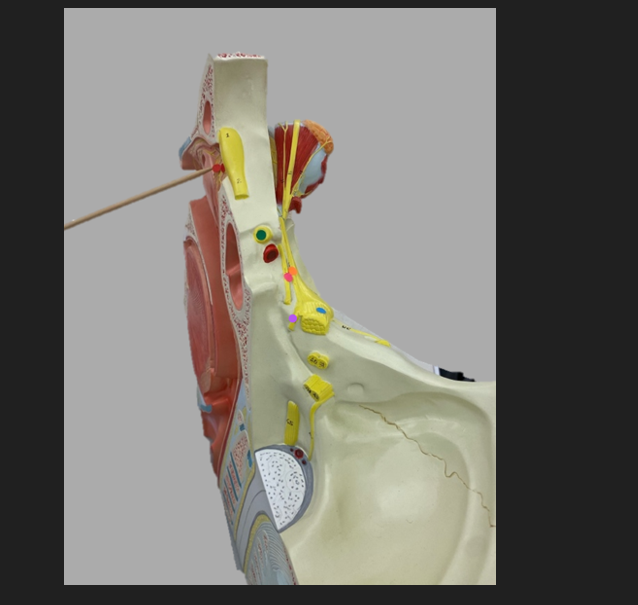

green dot

spinal nerve

orange dot

ventral root

pink dot

dorsal root

blue dot

dorsal root ganglion

red dot

dorsal ramus

yellow dot

ventral ramus

purple dot

anterior median fissure

red dot

posterior (dorsal) horn

purple dot

lateral horn

dark blue dot

anterior (ventral) horn

orange dot

dorsal column

yellow dot

lateral column

dark green

anterior column

line green and pink doit

gray commissure

light blue dot

posterior median sulcus